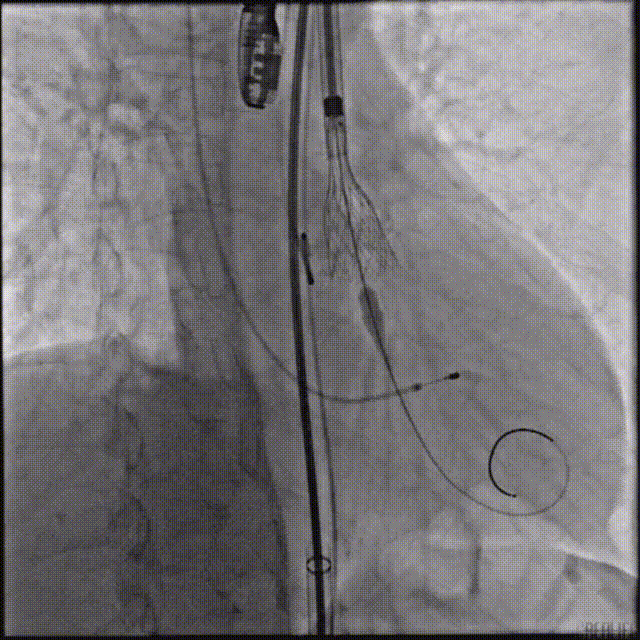

第一次释放到工作位后瓣膜下滑,回收调整位置后选择高位再次释放,最终造影显示瓣膜形态、位置良好,冠脉血流灌注正常,超声提示少量瓣周漏。

瓣膜工作位评估

术后根部造影

主动脉狭窄及反流是老年人群体较为常见的一种疾病,其严重影响患者的生活质量和生命安全。近年来,随着TAVR技术在国内的普及,主动脉瓣狭窄及反流患者有了更多的治疗选择。本例病人为主动脉瓣重度狭窄,手术指征明确,术前解剖形态评估适宜行TAVR手术。经李火平教授结构性心脏病团队的综合评估,结合心内科、心外科、超声科、麻醉科、影像科、ICU、神经介入中心等多学科团队的讨论意见,最终决定为患者施行TAVR手术治疗。手术过程中,TaurusElite输送系统在保持回收性能稳定的同时兼具优异的柔顺性,顺利完成过弓、跨瓣等操作。面对该病例复杂的解剖结构特点,瓣膜释放过程中可能出现瓣膜下滑的风险,增加了术中释放瓣膜的难度。TaurusElite瓣膜系统具有多次可回收、回收后可重新跨瓣等设计特点,让术者释放过程中更有信心,能降低手术风险,减少并发症的产生,从而让患者得到更好的预后。本例患者瓣膜释放过程出现位置偏低情况,通过可回收功能重新定位释放,最终瓣膜释放位置良好,冠脉血流灌注正常,术后压差明显降低,仅有少量瓣周漏。术后病人状态良好,各项生命体征平稳,准备安排出院。